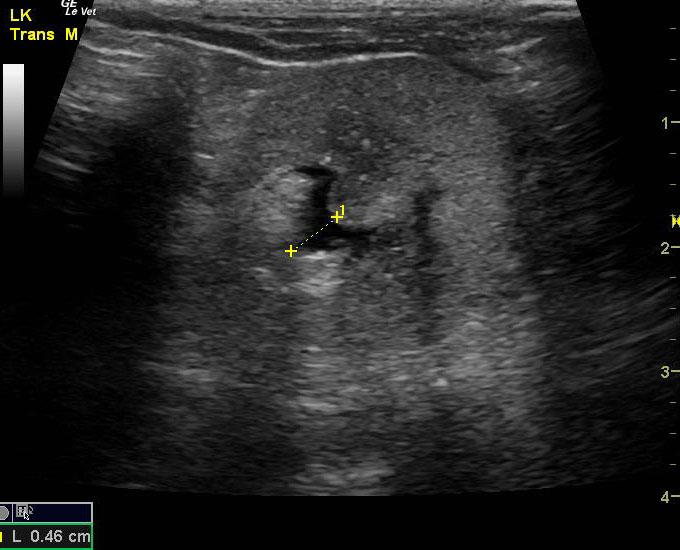

A 14-year-old neutered male Pomeranian dog was presented for evaluation of pollakiuria, diarrhea, inappetence, and lethargy. Abnormalities on physical examination included a painful, enlarged and symmetrical prostate, a very large and firm urinary bladder that could be expressed, and a grade III/VI heart murmur. On survey thoracic radiographs, calcification of the prostate gland was evident.

A 14-year-old neutered male Pomeranian dog was presented for evaluation of pollakiuria, diarrhea, inappetence, and lethargy. Abnormalities on physical examination included a painful, enlarged and symmetrical prostate, a very large and firm urinary bladder that could be expressed, and a grade III/VI heart murmur. On survey thoracic radiographs, calcification of the prostate gland was evident.